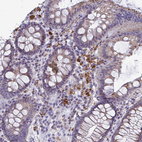

Immunohistochemical staining of human cerebellum shows strong positivity in neuropil.